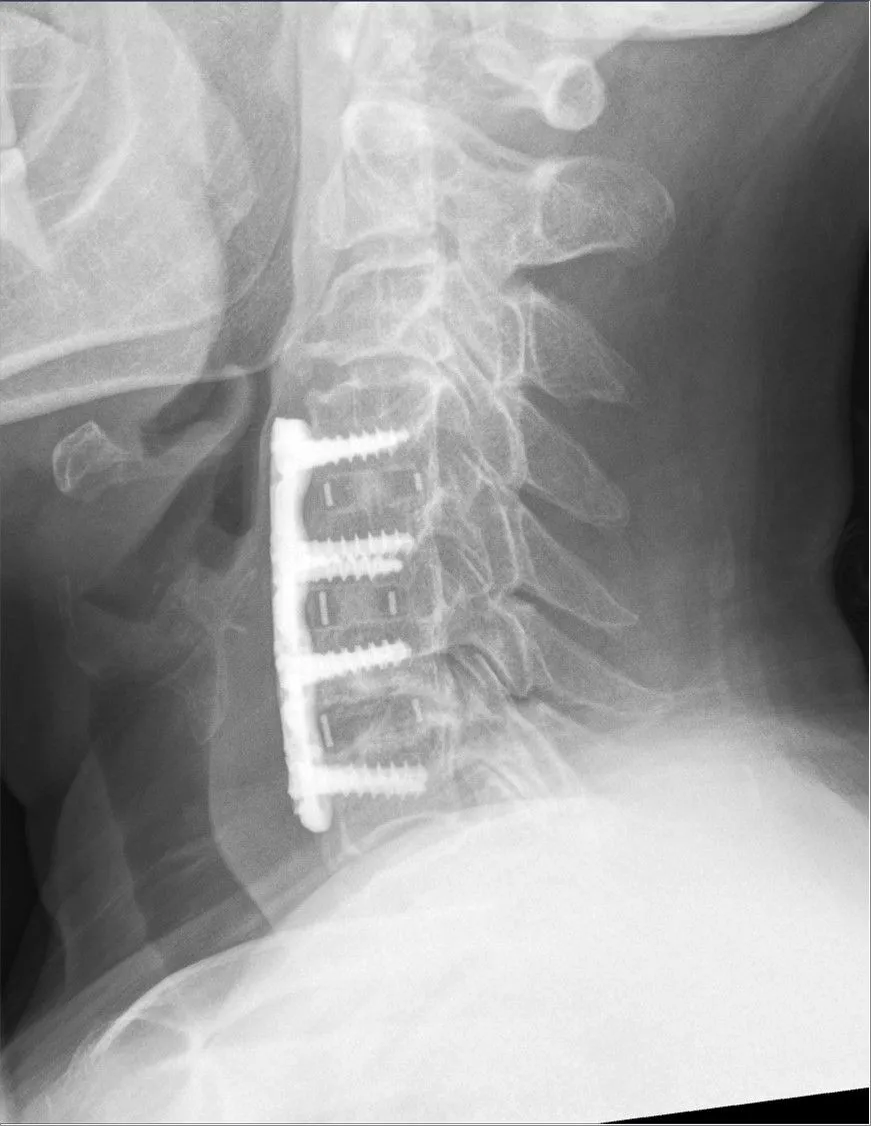

cervical fusion known as ACDF

Artificial discs attempt to solve the ASD problem by preserving motion (ACDF vs. artificial disc). However, they introduce a new set of risks while retaining many of the old ones:

• Failure and Migration: ADR involves implanting a mobile disc made of metal and plastic.Complications include disc migration, failure to bind to the bone, or fracture of adjacent vertebrae, particularly in patients with osteoporosis or osteopenia.

• Persistent Symptoms: If the nerve decompression during the surgery is incomplete or the disc alignment is improper, the procedure can fail, resulting in persistent neck pain and cervical radiculopathy.

ASD: While proponents claim better results,meta-analyses show that while the rate of subsequent adjacent-level surgery favoring disc replacement emerges around five years, the risk of ASD and the need for reoperation still exists, proving it is not a perfect solution.